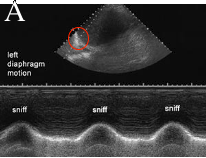

These two images are from a study called a 'sniff test'. This is done to document motion of the diaphragms. Image A shows the left diaphragm, which has the detector overlying it (oval). When the patient sniffs, the graph at the bottom shows normal motion. Image B shows no motion, or paralysis.